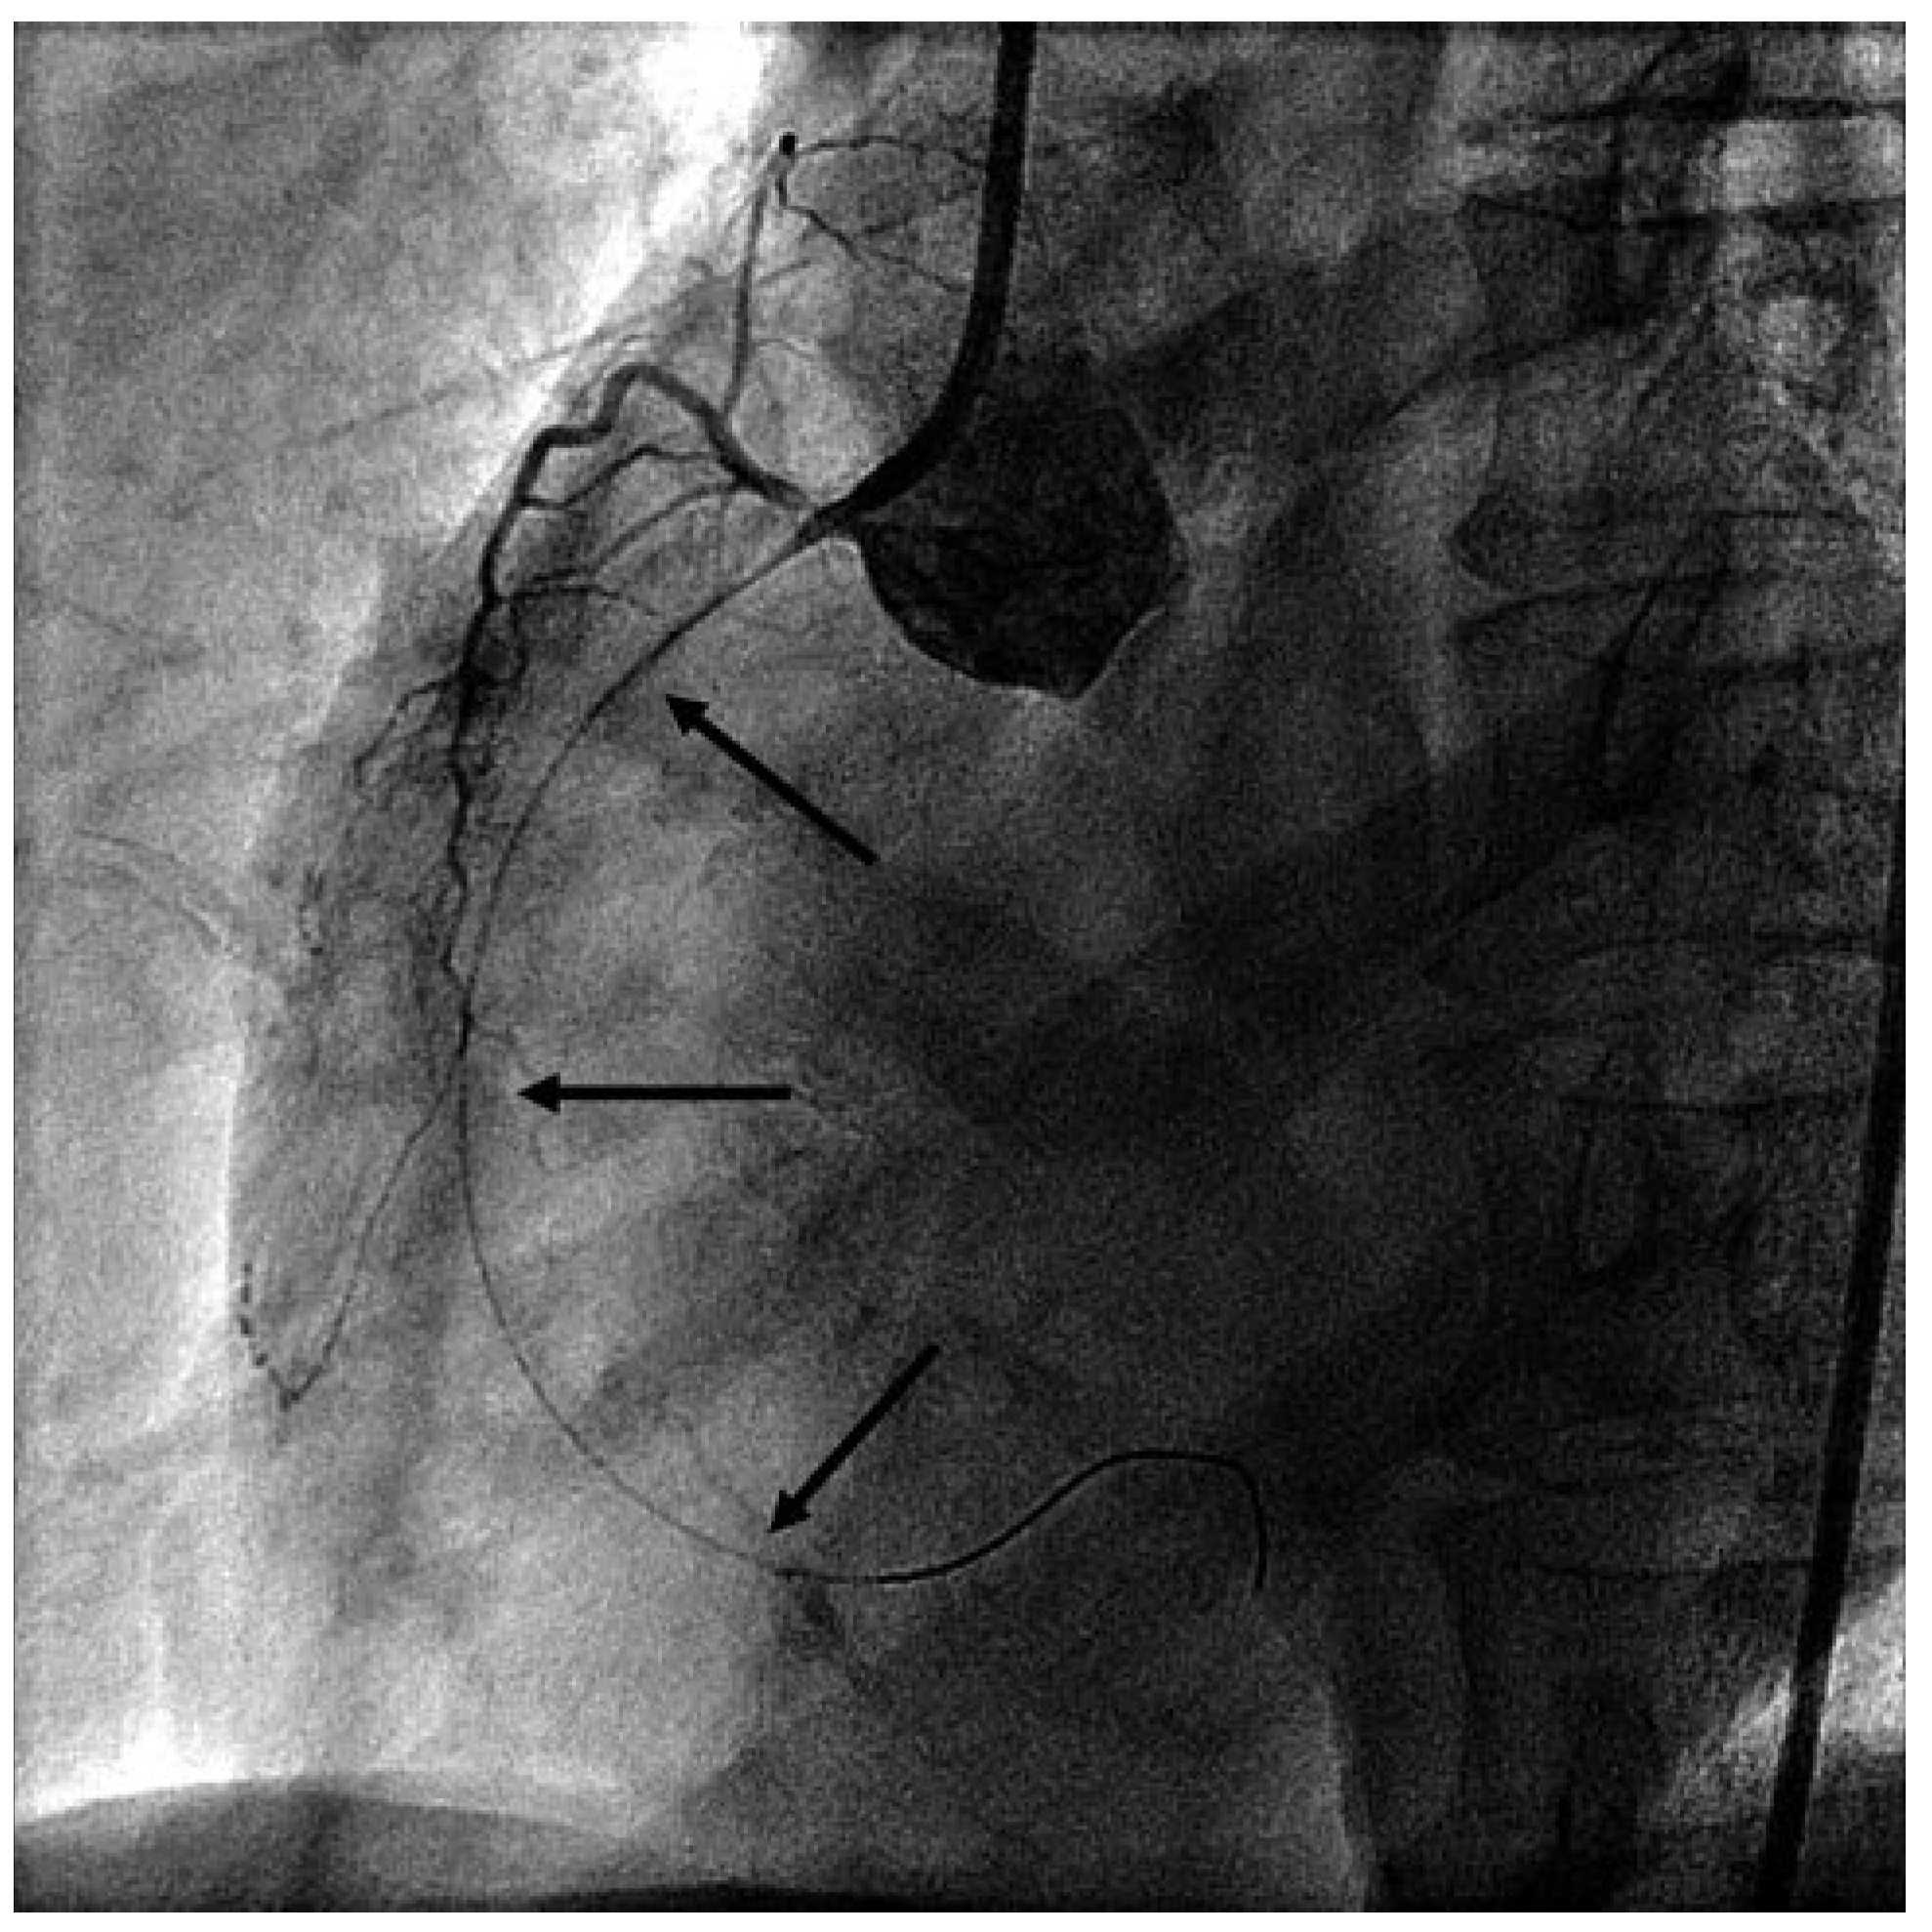

Presenting ECG changes (inferior ST-elevations) and rising cardiac enzymes, the patient was transferred to the acute care hospital and cath lab. Emergency coronary angiography showed severe stenotic lesions in the proximal right coronary artery (RCA) (Figure 1), in the proximal left anterior descending artery and in the diagonal and marginal branches. Due to cardiogenic shock and inferior ECG changes, a percutaneous coronary intervention in the RCA was organised. After engaging the RCA with the guide catheter, total occlusion of the RCA was observed. The coronary wire was immediately placed in the distal RCA but this failed to restore the flow (Figure 2).

Due to further haemodynamic deterioration an intraaortic balloon pump was placed. At this point review of the angiogram led us to suspect spasmodic occlusion of the RCA due to guide catheter and wire irritation. Intracoronary nitroglycerin (NTG), adenosin and verapamil were administered. The wire was pulled as far as the mid-RCA, after which measures flow was restored in the RCA (Figure 3) and the patient’s haemodynamic status stabilised. Reangiography of the left coronary artery showed resolution of the previously observed spasmodic lesions, and finally variant angina (prinzmetal angina) was diagnosed.

Figure 2. LAO view of the RCA: occluded RCA after coronary guidewire placement in the distal artery.